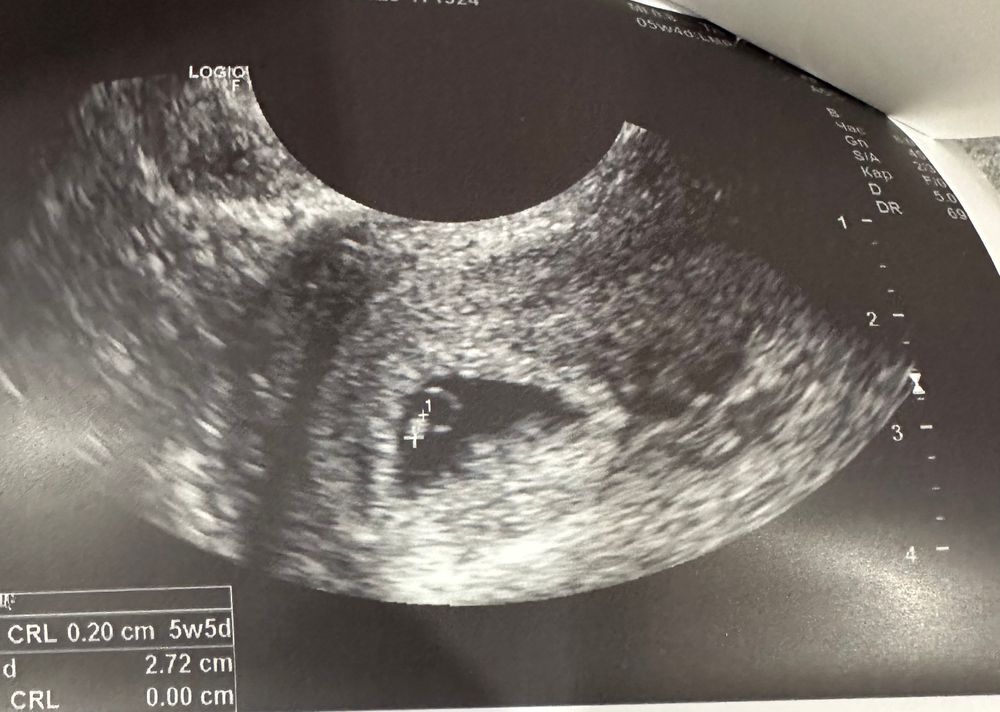

Изображение 5,4 недельки